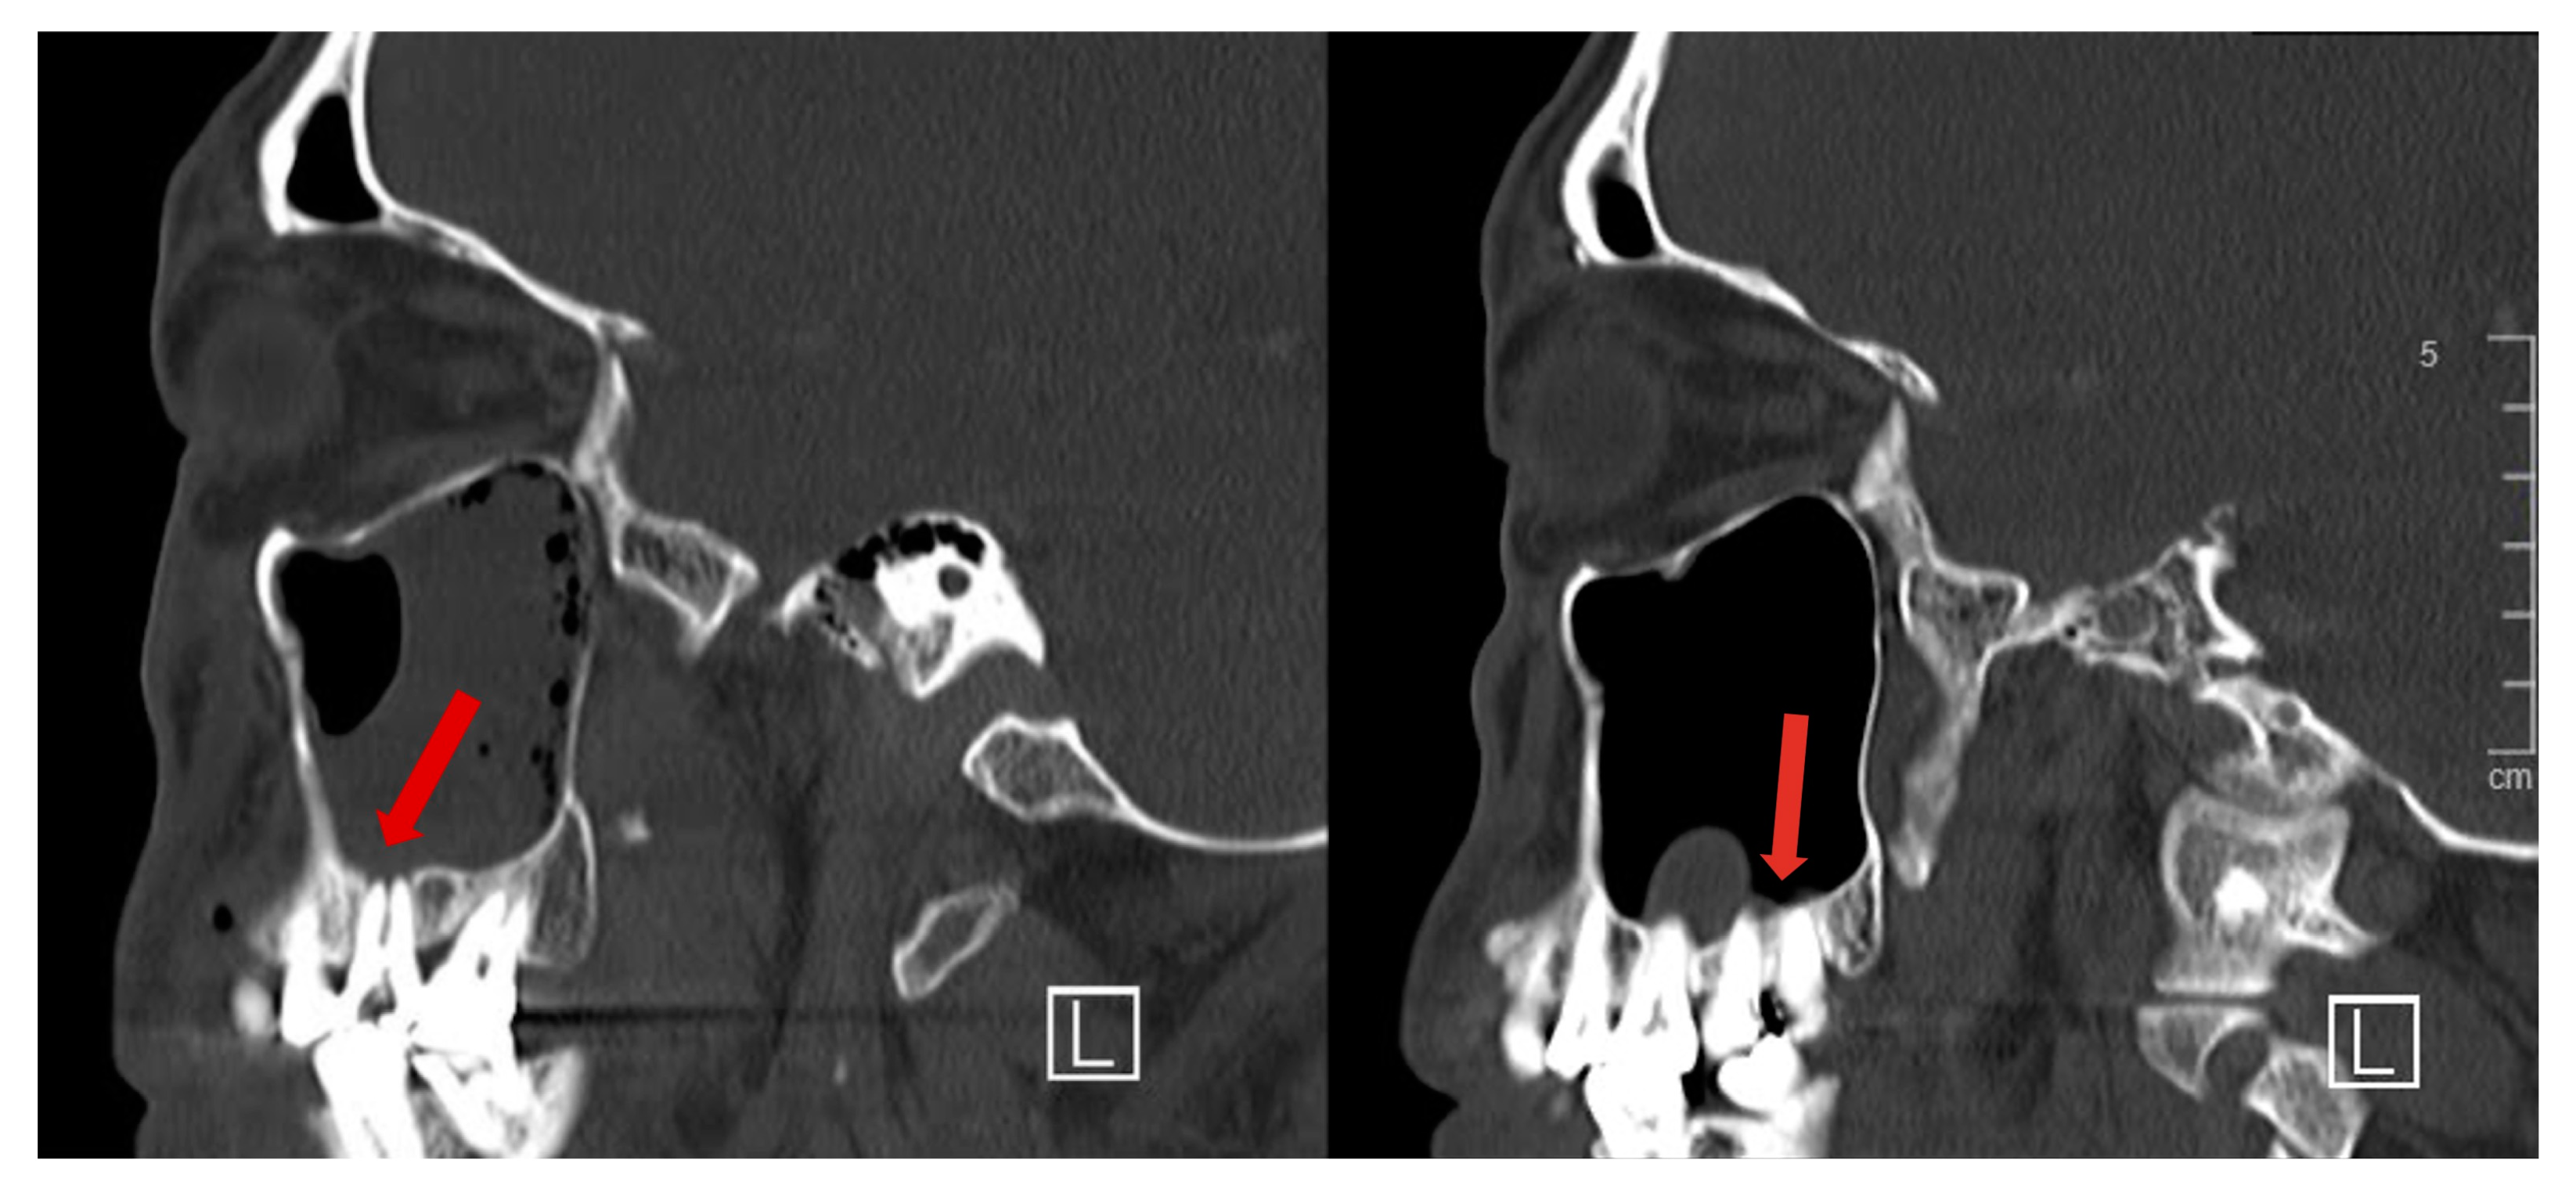

Figure 3.

Sagittal CT images from the same series showing projection of maxillary tooth roots into the maxillary sinus, with dehiscent overlying bony covering (red arrows).